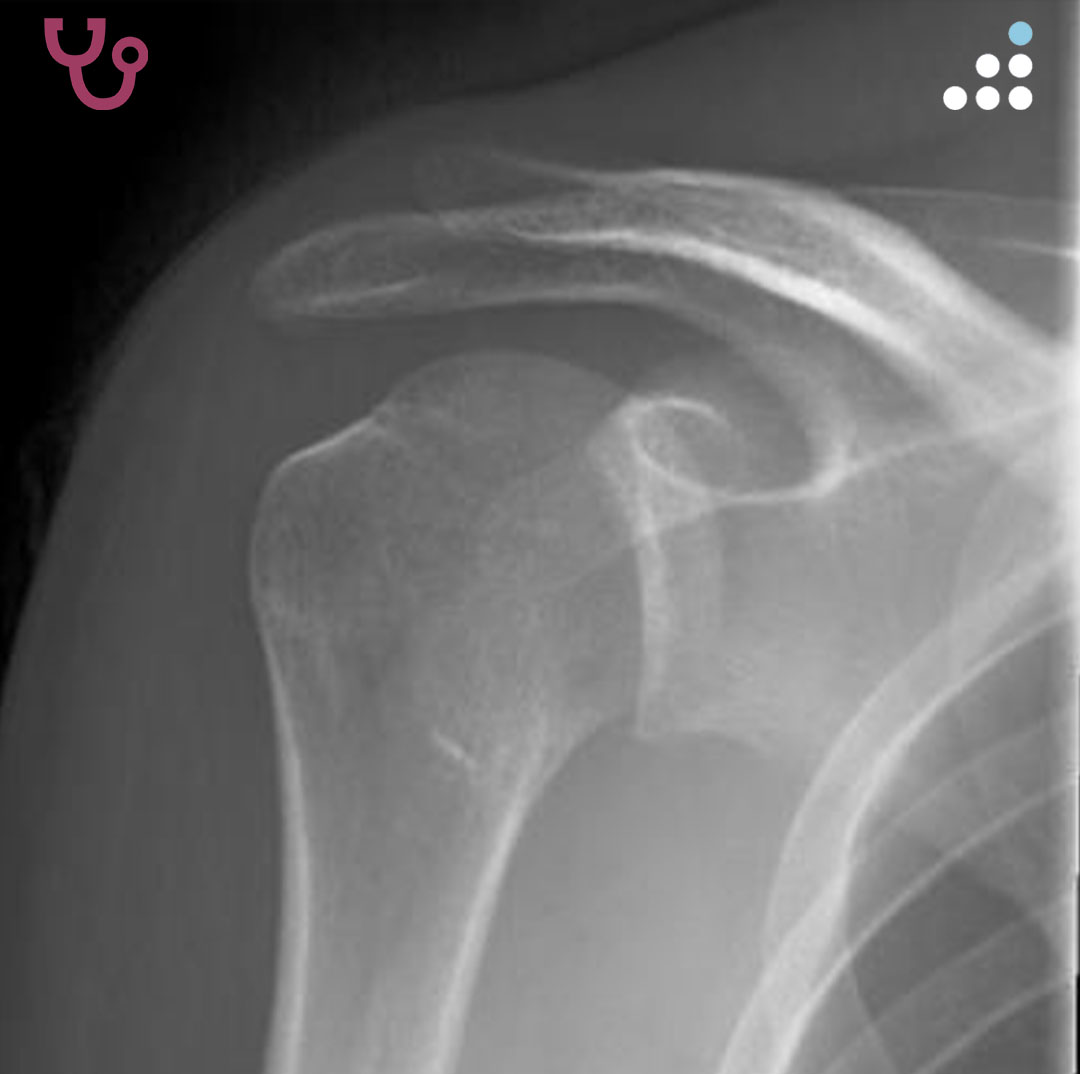

@orthobullets If there is still some cartilage left on the reverse Hill Sachs I’ve had some luck with doing a humeral head osteoplasty. I’ll use allograft chips or cement to backfill the defect after I tamp up articular surface and then try to get everything repaired especially in young pts